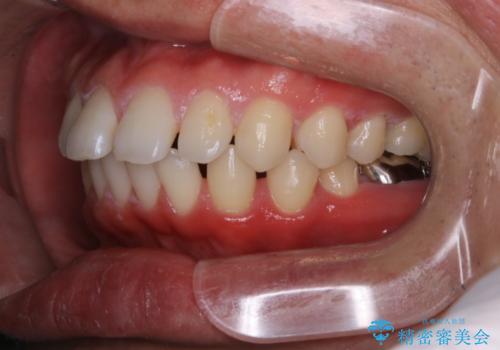

- 全体的に歯と歯の間に隙間があるのが気になるとのことで来院されました。インビザラインでの矯正治療をご希望されました。

隙間については、前歯と奥歯に多数あります。また、上下前歯は、外側に少し倒れているため隙間を閉じつつ、前歯を内側に引っ込めて並べることになりました。